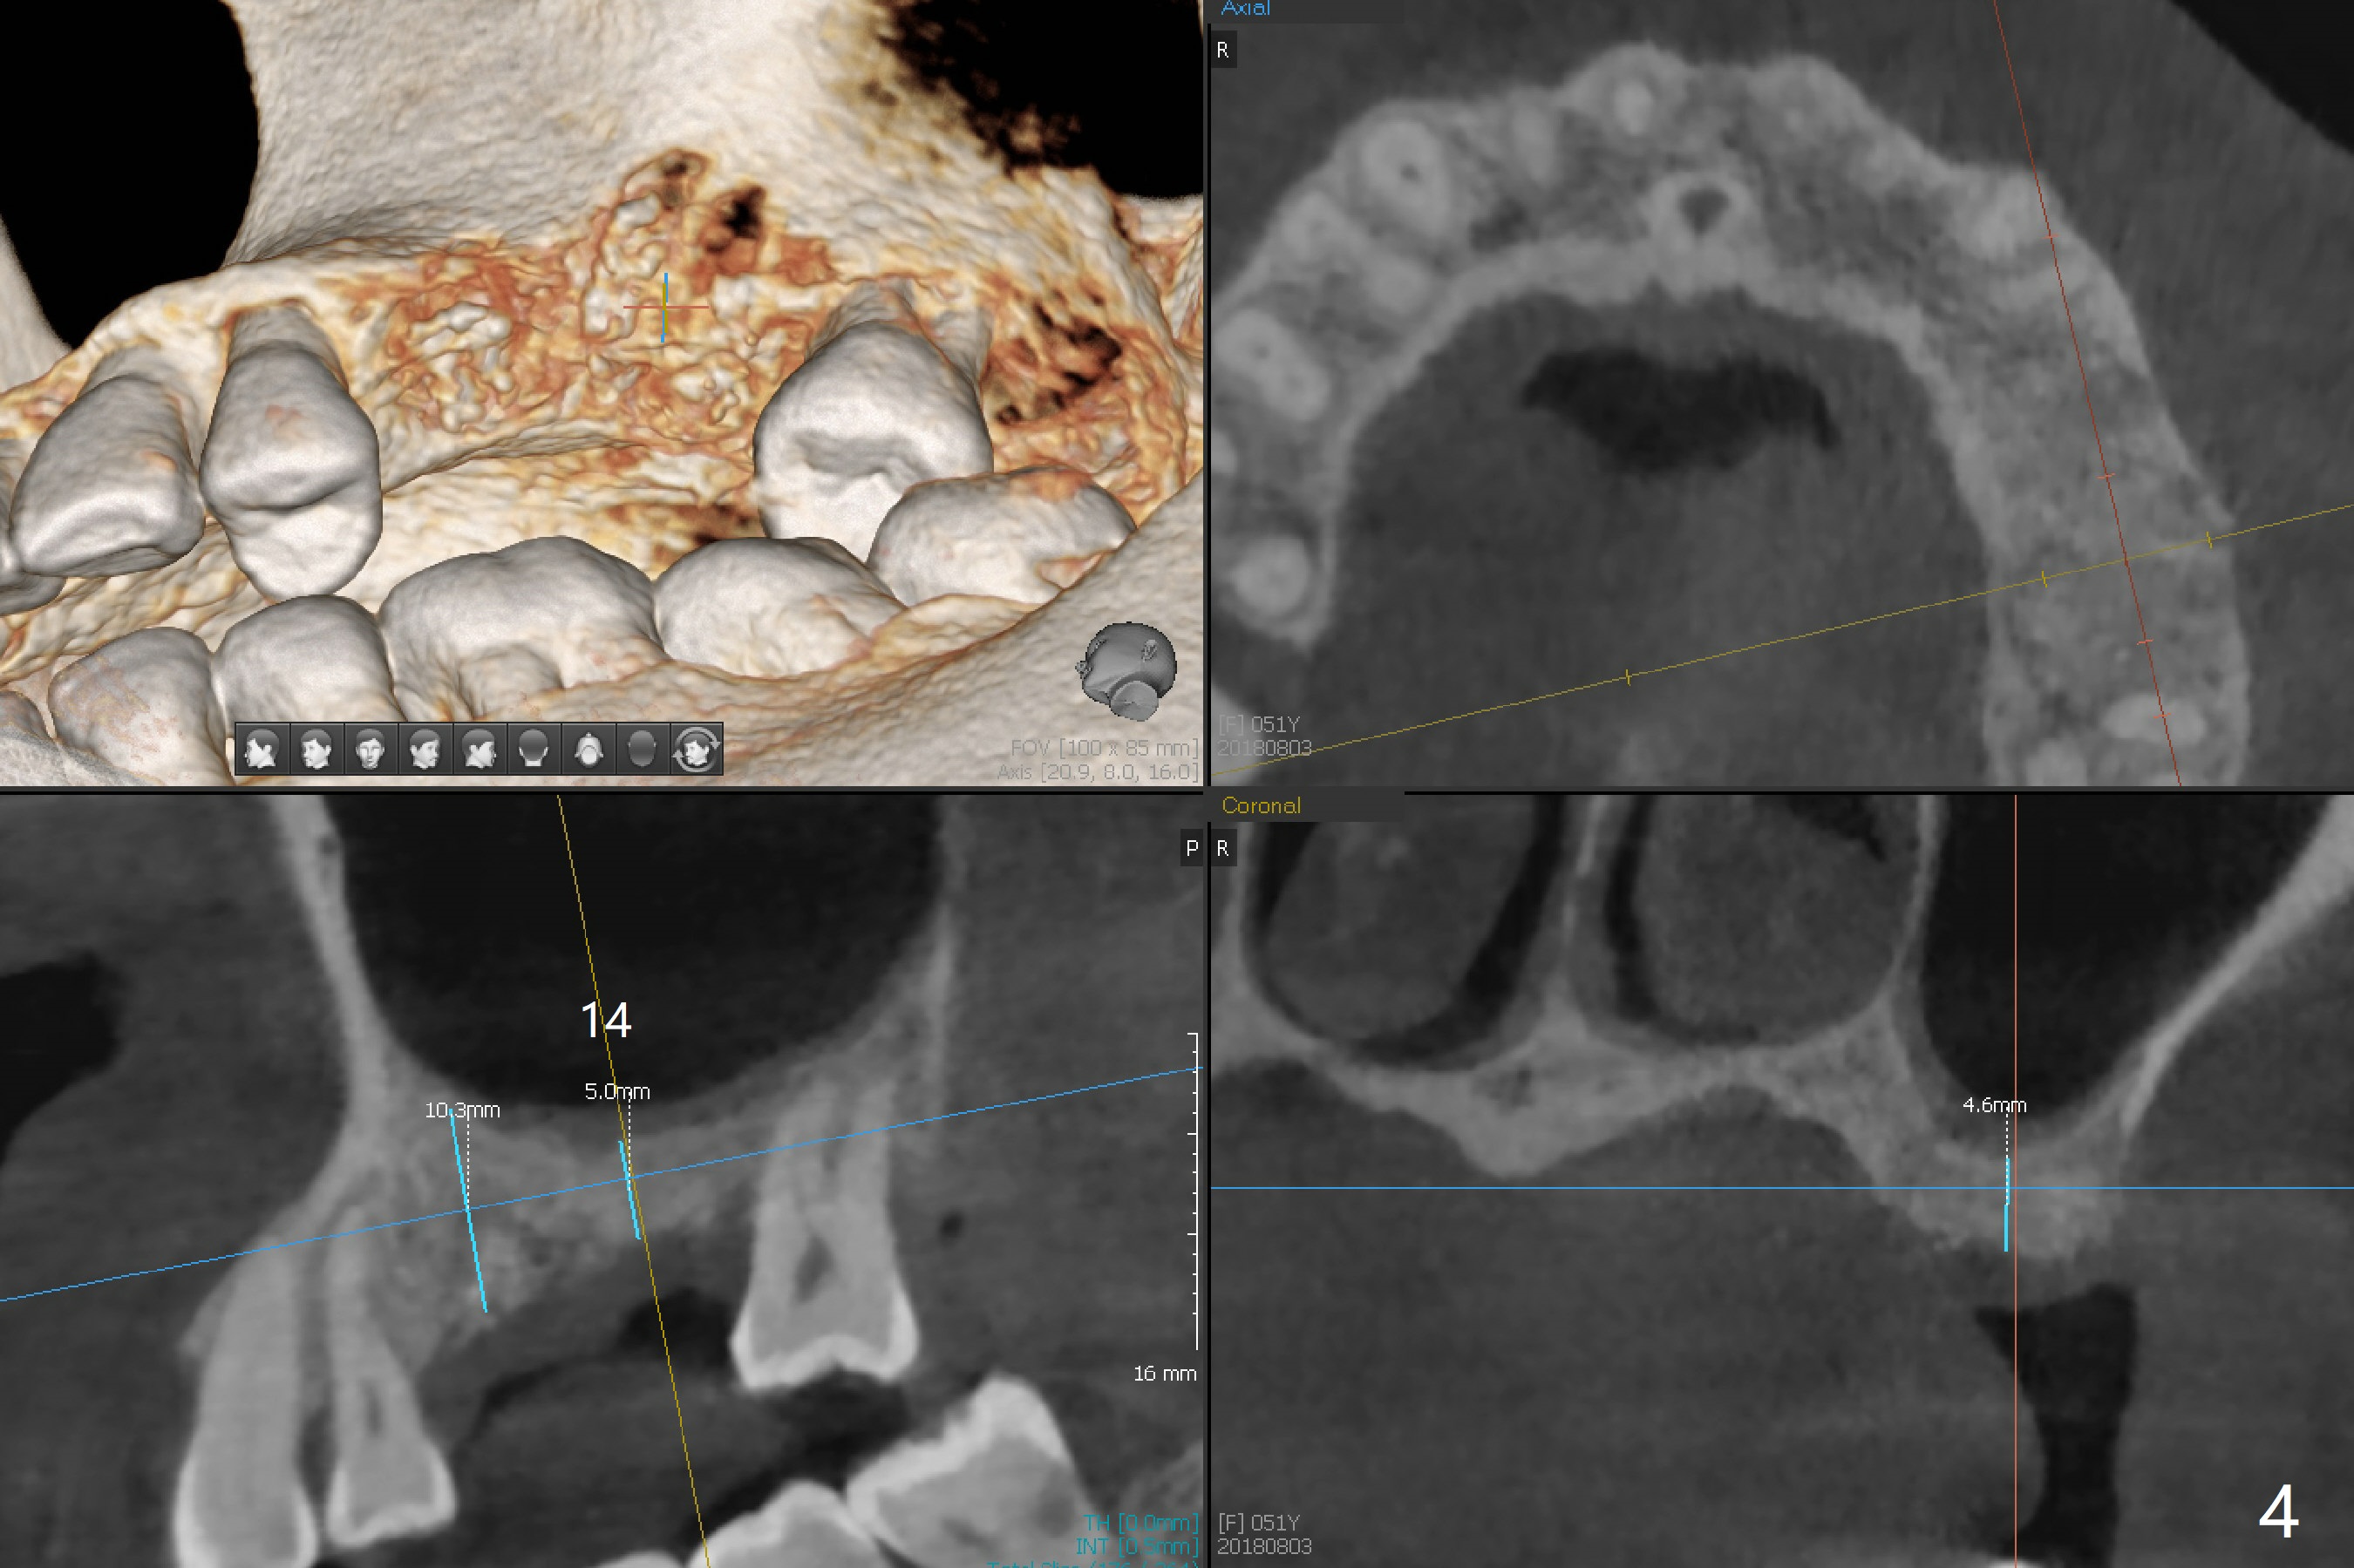

A 51-year-old woman with apparent chronic periodontitis (Fig.1) has the teeth #13 and 14 extracted with socket preservation in her home country 3 months earlier (Fig.3,4). The bone height associated with the residual roots at #2 is short; a 5x7.3 mm implant seems to be appropriate (Fig.2). Use Magic expanders and sinus lifter. The implant will be Magicore or consistent with those at #13 and 14. Prepare 2 pieces of PRF membrane for sinus lift and buccal defect. Osteotomy at #13 should be palatal (Fig.3 red line instead of blue one) to obtain more of the apical native bone for primary stability. Prescribe Augmentin after sinus lift. Osteotomy at #14 should be a little bit more distal because of the mesial shift of the tooth #15 (Fig.4). Early provisional to hold the edentulous space and limited ortho may be required. A guide will be made for #13 and 14.